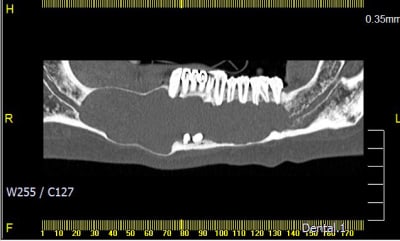

J'en ai déjà eu 3 comme ça, originaires de pays de l'est voir de l’extrême-est.

Un père pour un trou de 48 à 36 et son fils autour d'une 43 incluse. (origine génétique ?)

Et un autre au niveau latéral doit.

Idem adressé au CHU le plus proche.

Bon je sais , ça fait un peu le concours de celui qui à le plus gros ... kyste !!

Qui dit mieux ?